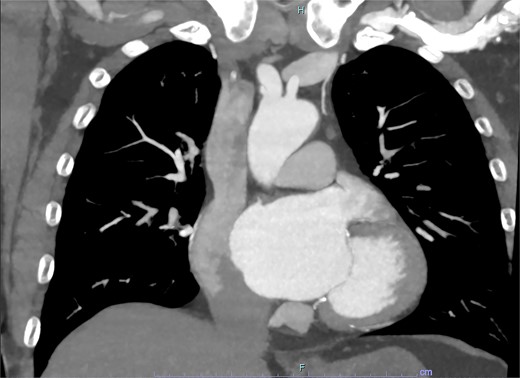

On arrive to the emergency department, the patient was found to be hypertensive with a blood pressure of 220/120 mmHg. Physical examination of the patient revealed no significant clinical findings. Serial troponins with corresponding ECG’s were undertaken which demonstrated no new evidence of myocardial ischaemia. Based upon the patient’s symptomatology, he underwent a CT aortogram which demonstrated a dissection arising from the proximal brachiocephalic artery. No dissection was noted in the ascending aorta, and there was no evidence of the brachiocephalic artery dissection extending into the subclavian or carotid arteries (Figs 1–3).

Axial slice from CT aortogram in greater detail of the dissection flap.